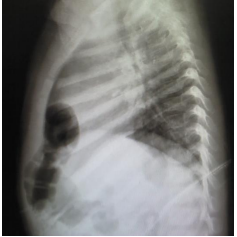

Menina de 1 ano apresenta tosse e coriza nasal hialina há 5 dias, sem febre. Exame físico: bom estado geral, frequência cardíaca de 120 bpm, frequência respiratória de 38 irpm, murmúrios vesiculares presentes e simétricos, com roncos transmitidos de vias aéreas superiores difusos. Antecedentes pessoais: 2 episódios de pneumonias tratadas ambulatorialmente, com 6 meses e 9 meses de idade. Raio x de tórax: imagens a seguir:

Assinale a alternativa que apresenta a principal hipótese diagnóstica.